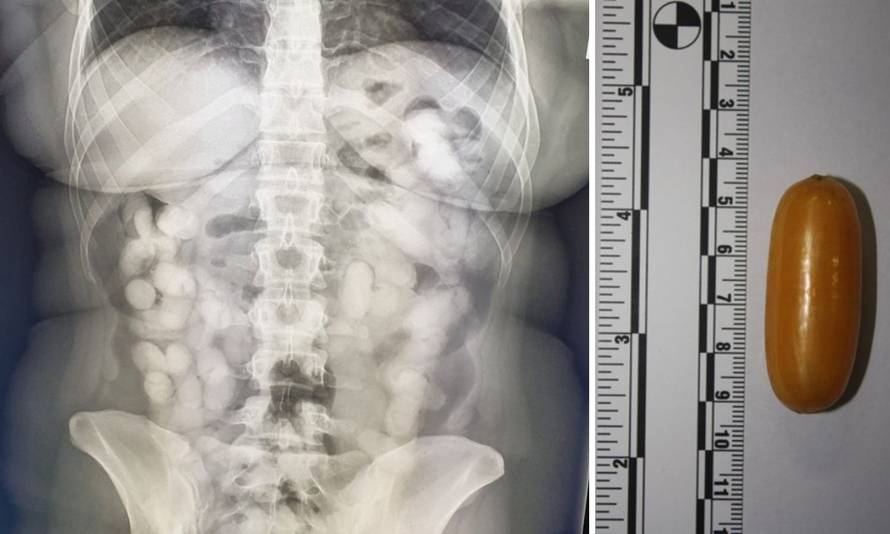

Ekskluzivne fotografije: Ovo je Brazilka koja je progutala kilu koke, doveli je u Veliku Goricu

Brazilka je u Zagreb stigla iz Sao Paula preko Lisabona što je odmah bilo sumnjivo carinicima jer je Portugal u Europskoj uniji, a carinski nadzor se ne provodi na putnicima koji dolaze iz zajedničke carinske unije